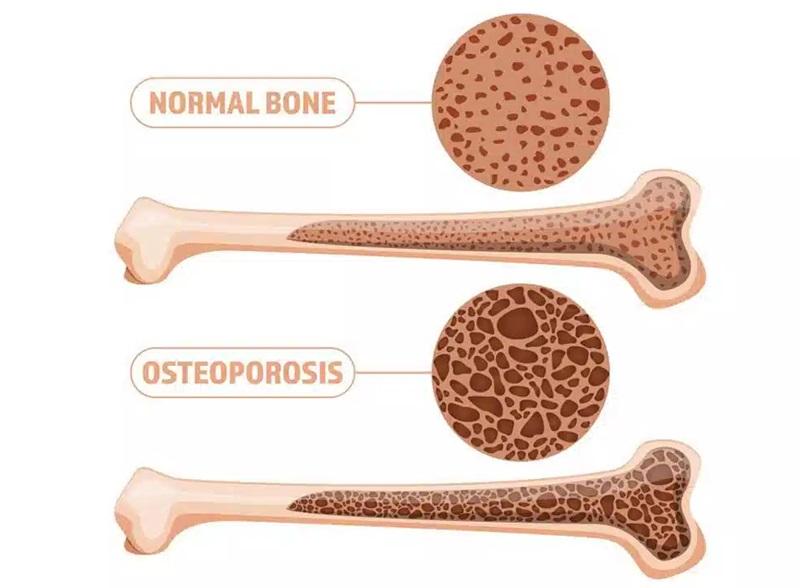

استئوپنی به معنای کاهش تراکم استخوان است. در این وضعیت، استخوانها ضعیفتر از حالت طبیعی میشوند، اما هنوز به مرحله پوکی استخوان نرسیدهاند. استئوپنی را میتوان مرحلهای بین سلامت استخوان و پوکی استخوان در نظر گرفت.

تشخیص استئوپنی معمولاً از طریق آزمایش سنجش تراکم استخوان (DXA یا DEXA) انجام میشود. این آزمایش غیرتهاجمی، میزان تراکم مواد معدنی در استخوانها را اندازهگیری میکند.

نتایج این آزمایش به صورت T-score بیان میشود:

- T-score بین -1 تا -2.5: نشاندهنده استئوپنی است

- T-score کمتر از -2.5: نشاندهنده پوکی استخوان است